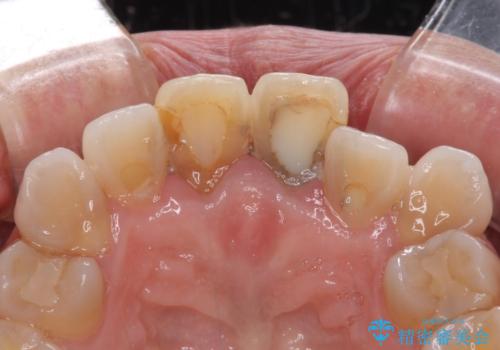

- 変色した前歯2本を気にして来院された患者様です。

右側の前歯は根管治療を行い、その後2本とも歯質に近い素材の土台を植立してオールセラミッククラウンにて補綴することとしました。

神経を取り除いた歯は、経年劣化により変色してしまいます。